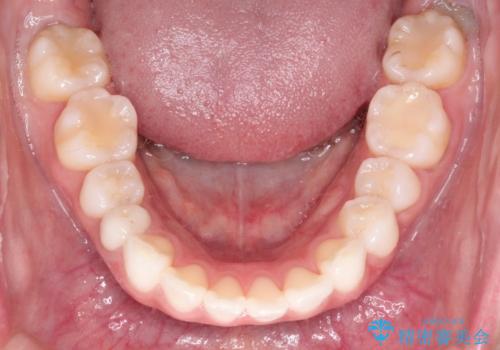

- 審美装置

- 2年1ヶ月

上下左右の歯を1本ずつ抜歯して、そのスペースを利用して口元を引っ込める計画としました。